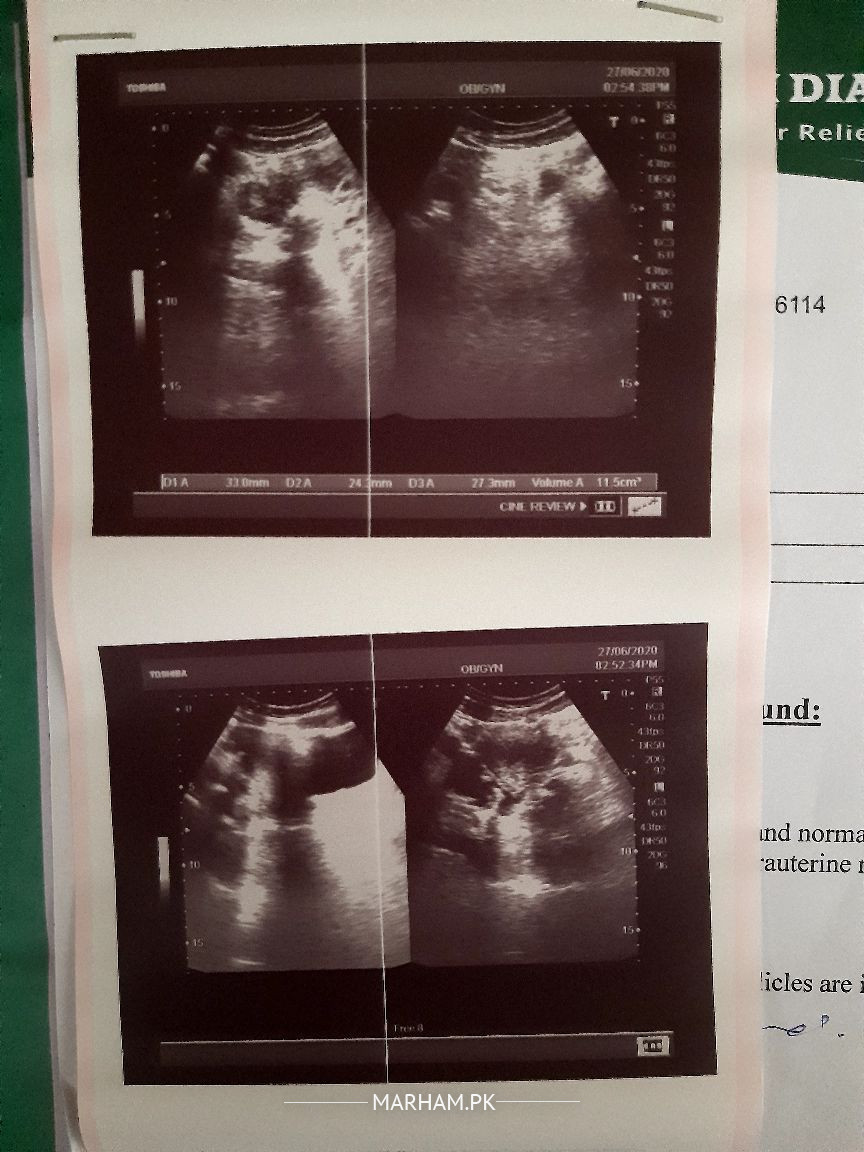

i am 25 years old 5.8 inches tall unmarried weighing 71 kgs. My mother and maternal grandmother had cyst issues my mother also have hyperthyroidism. in last dec my date was 13 but till 23 i didn't bleed. i visited a gynecologist in society she told me i have pcos and right ovary is typical polycystic. she prescribed primolute n for periods for 5 days but i bleeded on 24. ever since then my periods are regular. recently i had my periods on 29th day of my cycle. but this time i only bleeded for 2 days, on 3rd day very little blood was seen on washing , pad remained unstained on 4tg day i had brown discharge. i never had very heay bleeding ever but i use to bleed a little on 3rd day too. i had my harmones check in January they all are normal. today i visited a gynecologist in ultrasound my right ovary appeared large and bulky. she prescribed me folic acid n said yet the issue is not severe but can be in future and asked me to take folic acid every day and notice my cycle for 2-3 months.

mam with due respect ultrasound report is attached above.. have a look and suggest .

in pco there should b bilateral polycystic u dont have pco as such but at border line it could b. dnt worry continue folic acid one daily and try for normal conception